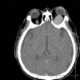

Nerve destruction by neoplasm

A brain tumor occurs when abnormal cells form within the brain. There are two main types of tumors: cancerous (malignant) tumors and benign (non-cancerous) tumors. [Source: Wikipedia ]